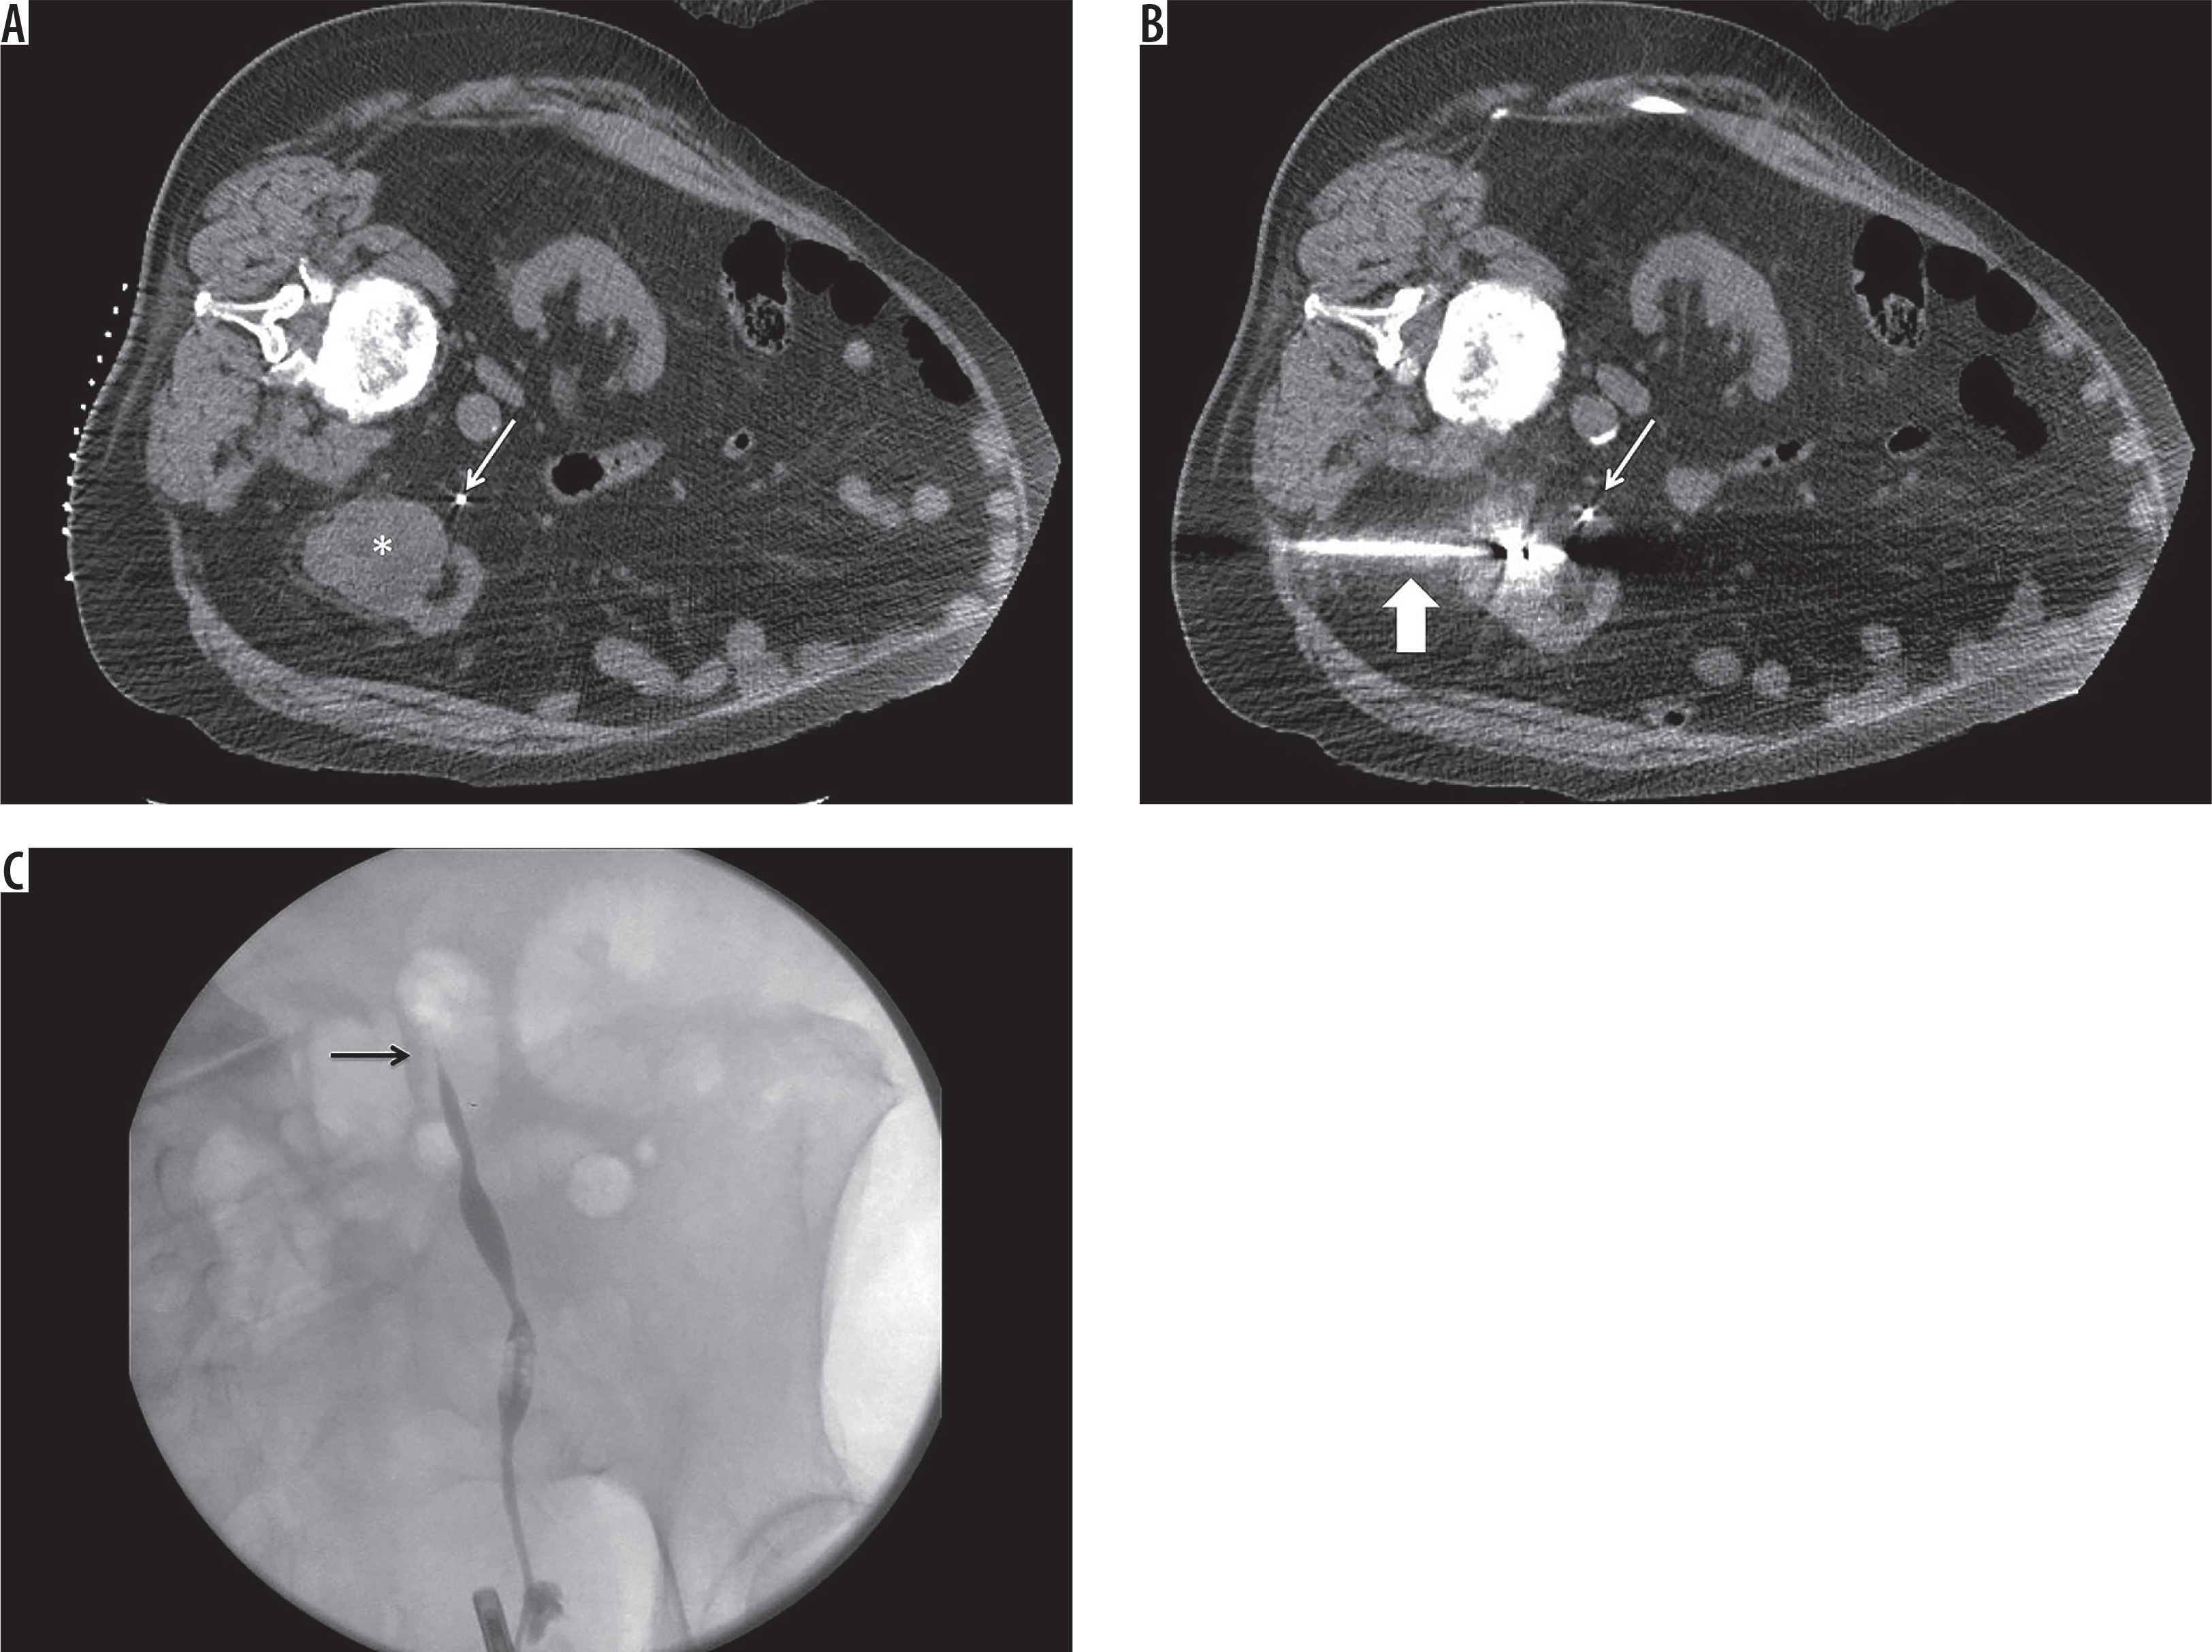

Figure 3

A) Axial unenhanced computed tomography (CT) scan of the abdomen at the time of ablation. Patient is in the left lateral decubitus position. White arrow indicates stent in the left ureter. White asterisk indicates renal cell carcinoma. B) Axial unenhanced CT scan of the abdomen at the time of ablation. Patient is in the left lateral decubitus position. White thin arrow indicates stent in the left ureter. White thick arrow indicates microwave ablation antenna. At the conclusion of the procedure, it was noted that the tubing connecting the bag of 0.9% normal saline to the ureteral stent became disconnected. As a result, it was likely that there was effective pyeloperfusion during treatment. C) Fluoroscopic images taken at the time of left retrograde pyelogram that demonstrate proximal ureteral stricture (black arrow)